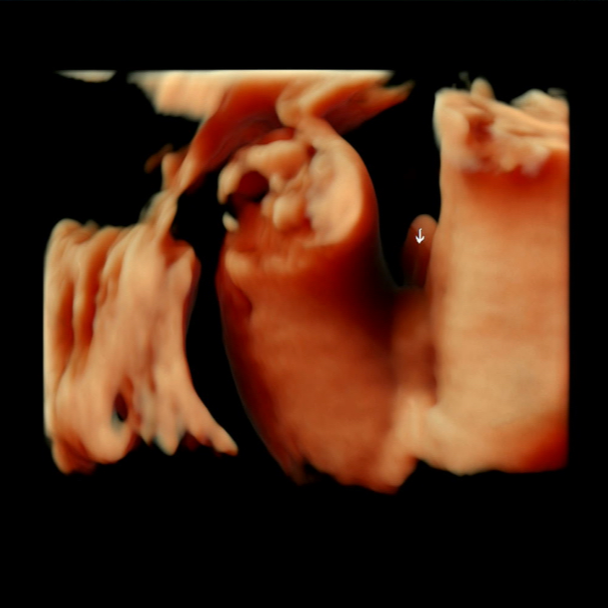

두둥-! 대망의 입체초음파 보는 날. 과연 우리 아들은 얼굴 잘 보여줄까???? DT에서 초코음료 포장해서 가는 길에 옴뇸뇸 얼굴 잘 보여죠~ 완주야~ 세뇌시키며 병원을 향했지. 다행히 올해 효성병원 초음파 기기가 다 바뀌어서 화질이 괜찮았다.

우리 아들 입체초음파 시작하자마자 바로 얼굴 보여줬고용.. 히히 눈도 떠 줬다! 손가락 발가락 5개도 다 확인하고 성별도 한번 더 확인 사살...